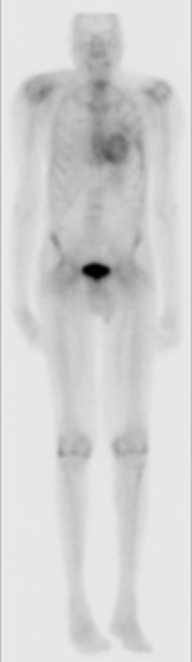

Cardiac Uptake on Bone Scan

• Amyloidosis —> Diffuse myocardial uptake

Amyloidosis